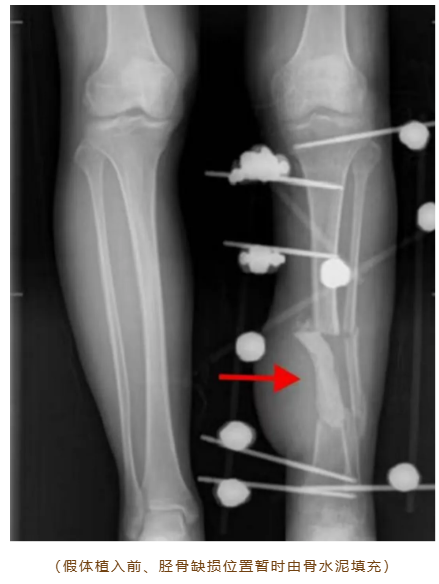

“不想取自身骨头,也怕进行骨搬运手术。”袁先生的顾虑很典型。自体骨移植需额外开刀、恢复慢;传统骨搬运易引发皮肤坏死、感染,治疗周期常常超过半年。针对其诉求,骨伤五科李敬矿主任医师、袁兆能主任医师、钟振东副主任医师、陈梦程主治医师团队经过慎重考虑,决定采用3D打印个性化金属假体定制修复方案。

团队术前研究发现,当时主流3D打印假体多为单侧偏心固定,易出现应力反应。为此,团队经过多轮力学模拟,创新性地采用“金属假体+髓内钉”中心固定模式,还在假体与骨端接触面设计侧翼固定,双重保障稳定性。据目前国内外媒体报道,该术式属于3D打印金属假体修复大段骨缺损的首次创新应用。

尽管术前通过3D建模实现了假体与骨缺损区的精准匹配,但手术仍遭遇挑战,袁先生因创伤导致骨质畸形,解剖标志、内部结构异于常规,这对假体植入角度、深度要求极高。然而,手术团队凭丰富经验,成功植入定制钛合金假体,再用髓内钉固定方式将假体和自体骨紧密连接一体。